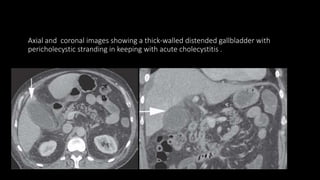

 CT is not routinely required but may be utilized as part of the investigation of

nonspecific abdominal pain or to assess for secondary complications of

cholecystitis.

• Gallbladder wall thickening (>3 mm).

• Biliary calculi may be visualized as foci of high attenuation within the gallbladder.

• Inflammatory stranding in the pericholecystic fat

• Pericholecystic fluid/focal enhancing collections will appear as a low-attenuation

collection surrounding the gallbladder.

• Locules of free gas adjacent to the gallbladder secondary to necrosis/perforation.

• Cholecystoenteric fistulae are rare.

Axial and coronal images showing a thick-walled distended gallbladder with

pericholecystic stranding in keeping with acute cholecystitis .